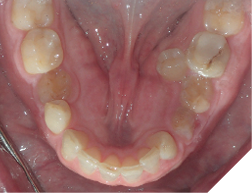

Fig. 2A

Fig. 2B

Fig. 2C

The majority of the orthodontic practices offer a period of “supervised retention” to their patients and communicates the customized retention recommendation with the patient’s general dentists. It is extremely important to work as a team to achieve long term clinical success in maintaining a functional bite and aesthetic smile. The general dentists continue to see their patients on a regular basis and have an opportunity to assess the orthodontic retainers and the bite after the supervised retention period is completed by the orthodontists. With great care, orthodontic retainers would serve for a long time (Fig. 1) without any major issues. However, in some cases, the failure to notice the clinical problems early on results in functional issues that would require a comprehensive orthodontic treatment to correct it (Fig. 2).